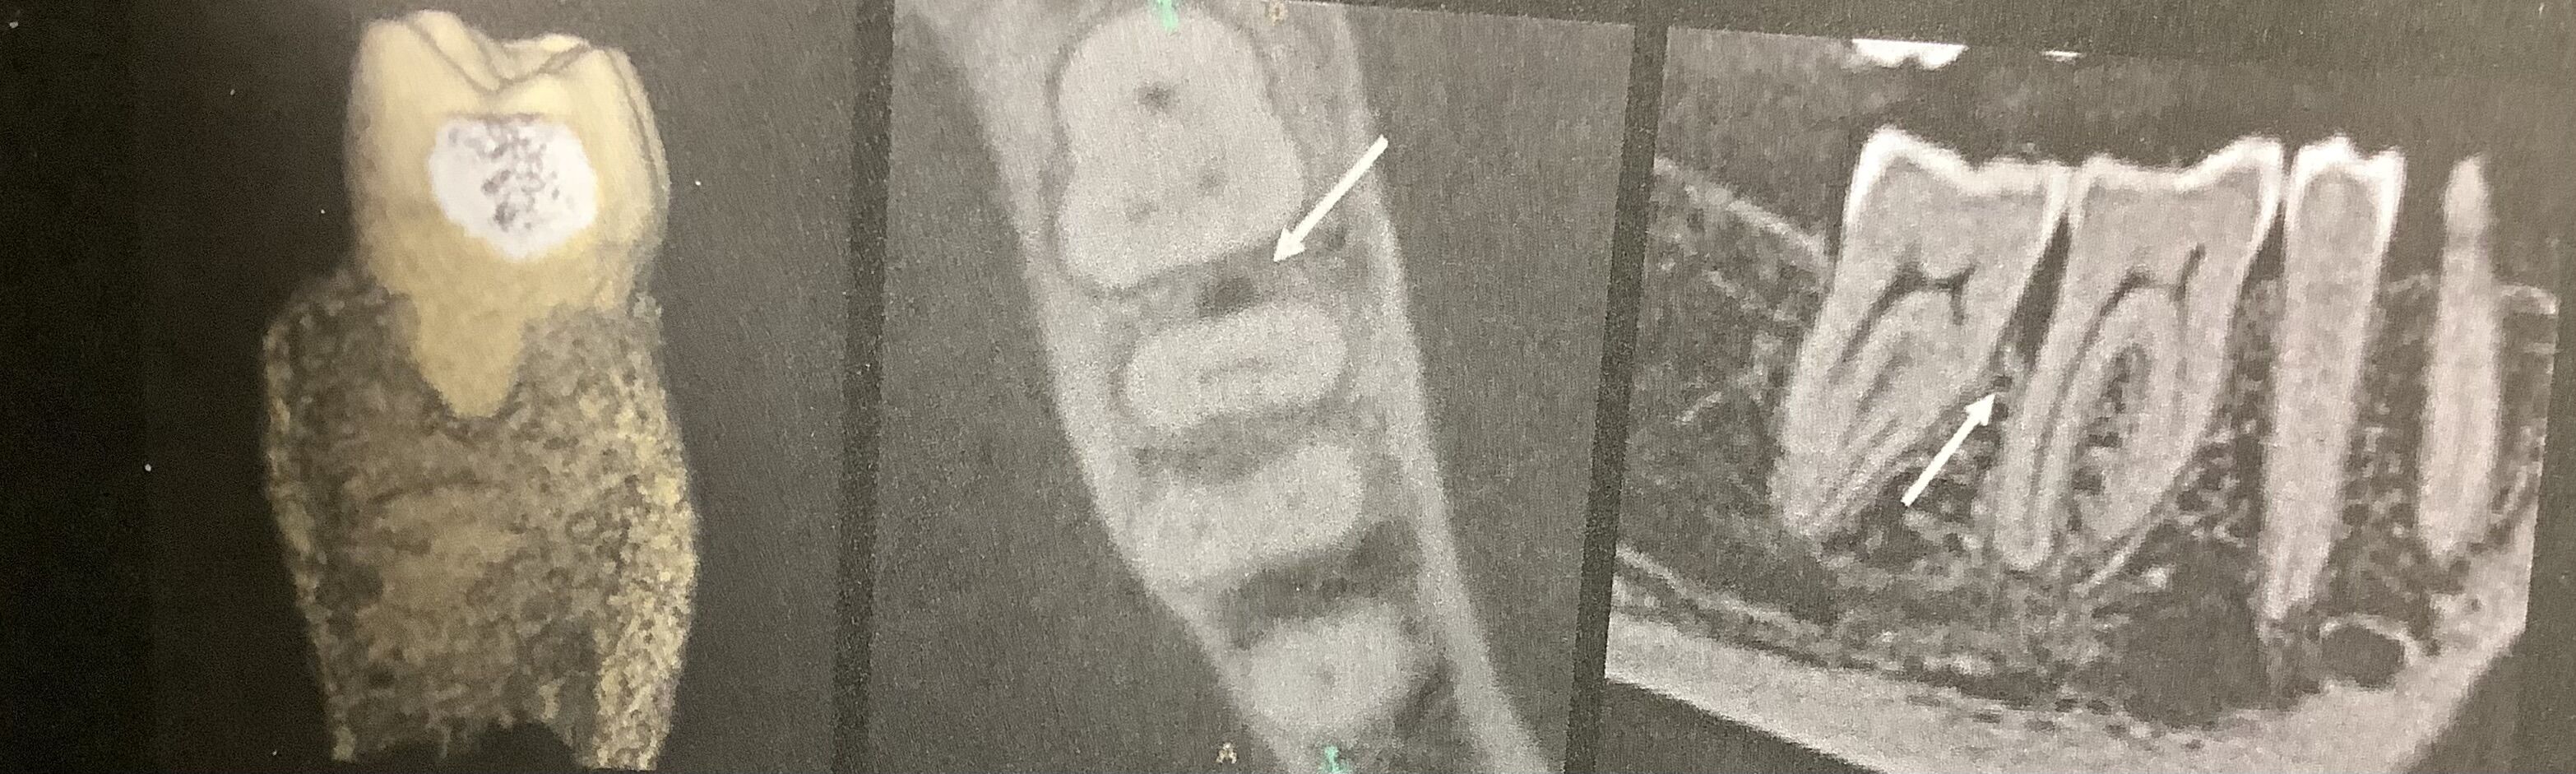

残念ながらCBCTであっても、

その解像ボクセルよりも狭いヒビでは写ってきません。

でも骨の減り具合からヒビの可能性やその深さを予想できます。

典型的なクラックでは狭くて、そこだけに現局したカゲが根っこに沿って見られます。

こんな風に。

CBCTでは他のものの重なりを避けられます。

様々な方向から向きを変えて見られます。